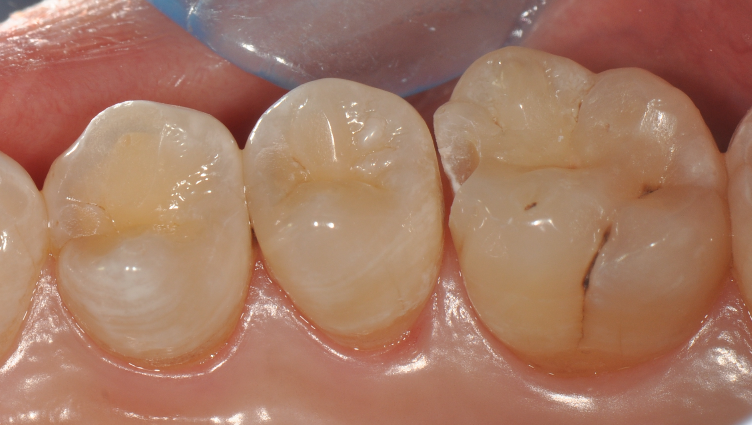

牙医-马小寒【实操病例】

右上6号牙位的近中,可见隐约龋坏